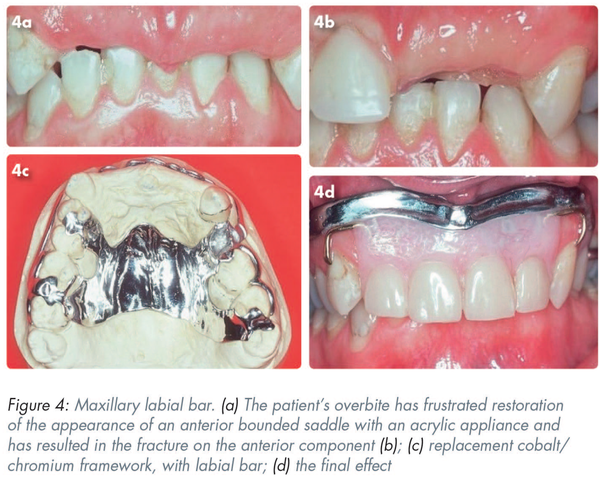

Figure 4 shows a labial bar being used in a situation where the patient’s complete overbite (Figure 4a) has frustrated the attempt to restore the appearance of an anterior bounded saddle with an acrylic appliance and has resulted in the fracture on the anterior component (Figure 4b). The replacement cobalt/chromium framework, with the labial bar, is shown in Figure 4c.

Figure 4d shows the final effect, where the denture teeth are “suspended” from the bar without interference with the occlusion. The teeth have been set closely to their original positions and are thus not interfering with the lip morphology or the function of the tongue. The labial bar is not visible nor are the gold TAWs giving retention on the canines.